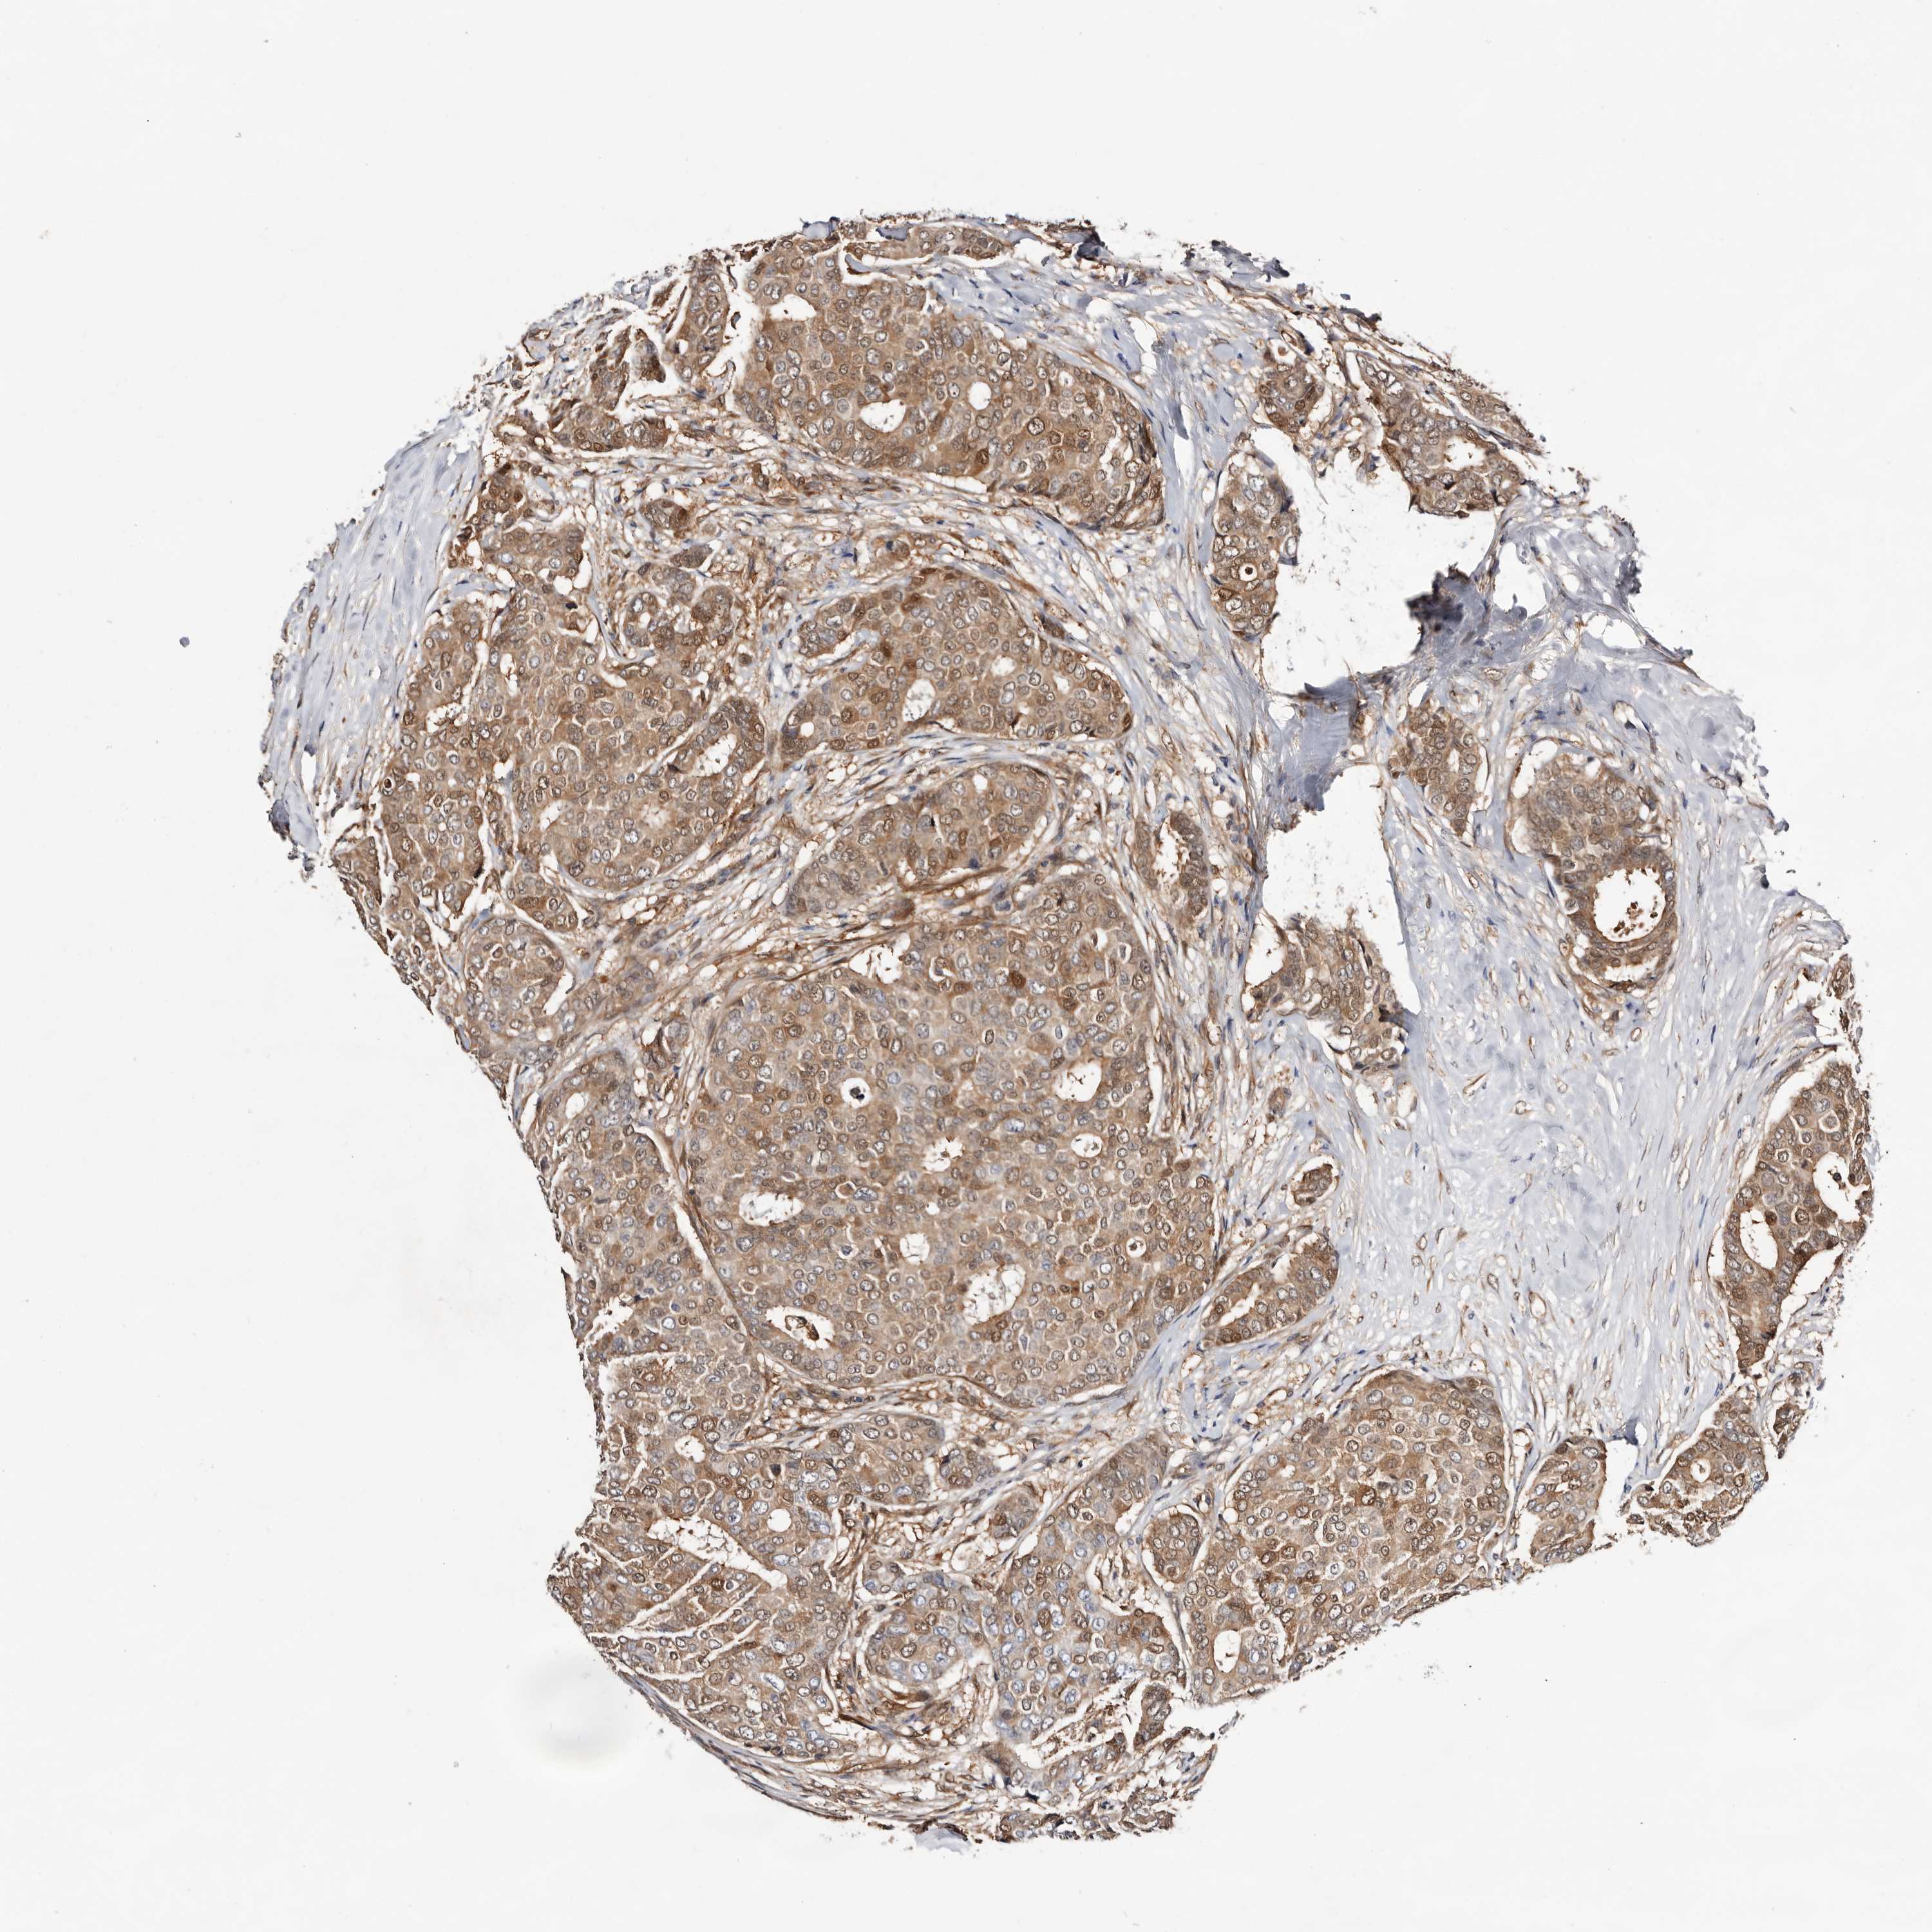

CANCER BREAST CANCER Show tissue menu

BRCA TCGA BRCA VALIDATION PROTEIN EXPRESSION

ANTIBODIES

AND

VALIDATION